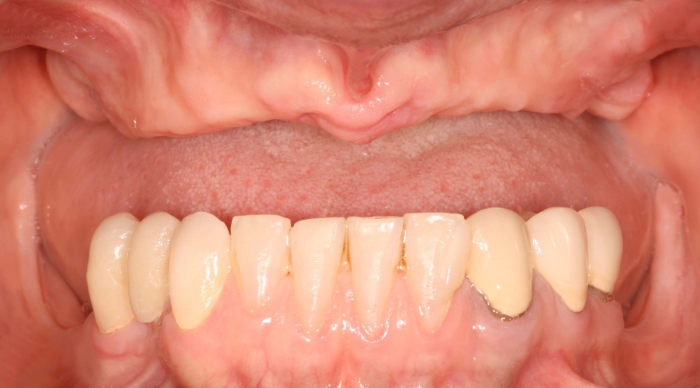

Imagem inicial